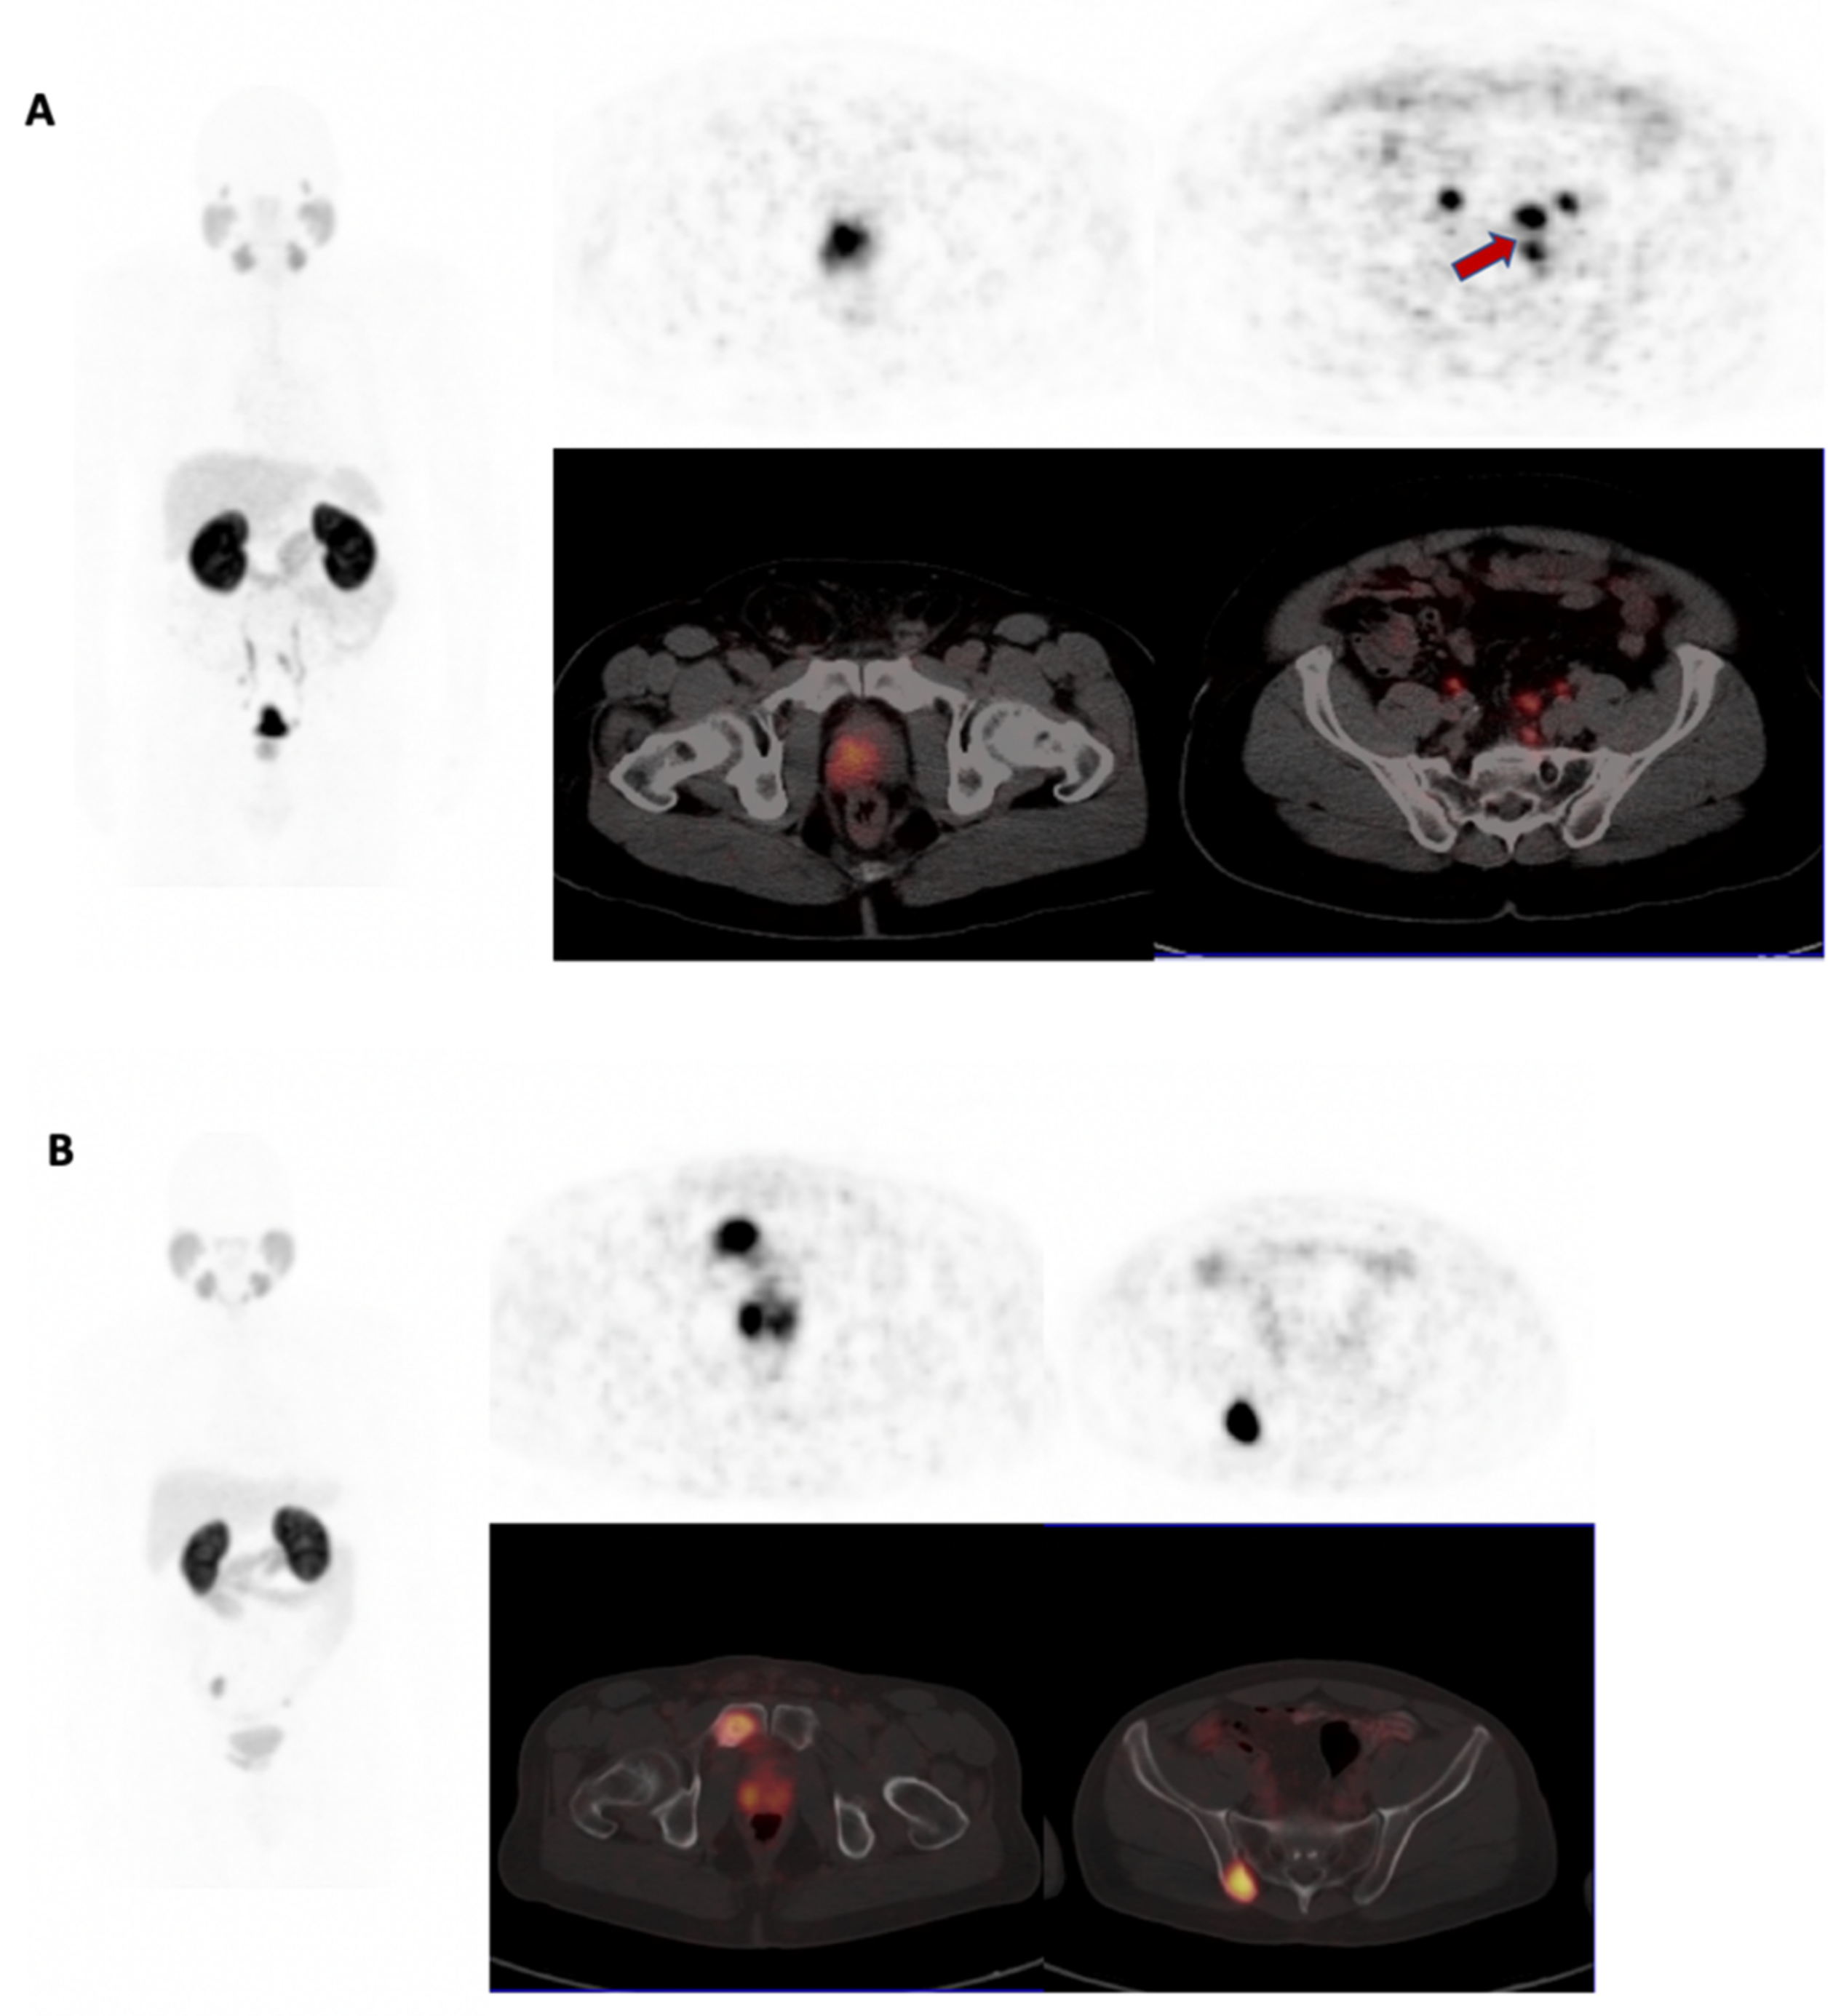

3.2. 68Ga-PSMA PET/CT Analysis

3.3. Comparison of BSA and WSA Males

3.3.1. Primary Tumor

3.3.2. Metastatic Involvement

3.3.3. Factors That Predicated for Extra-Prostatic Involvement